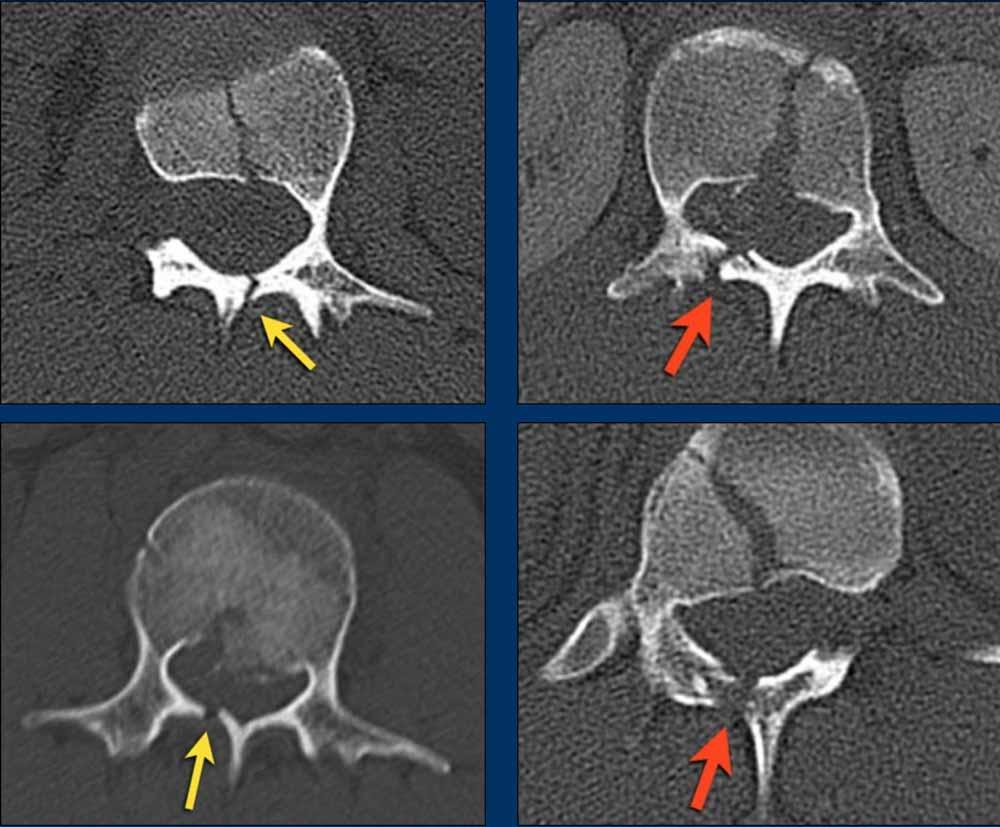

These images are of a young child with a spinal injury.

Findings

- Clear widening of the interspinous distance (yellow arrow)

- Black arrowhead: small avulsion fracture to the flexion distraction

- MRI better depicts the ligamentous injury, which was suspected on CT

Conclusion

Injury type B2

Scroll through the images.

What is the highest AO-type of injury?

Any additional findings?

- Subtle widening of the interspinous distance (white circle)

- Small avulsion fracture spinous process (yellow arrow)

- Compression fracture with involvement of one endplate and posterior wall (1+2 points)

Injury type B2 + A3